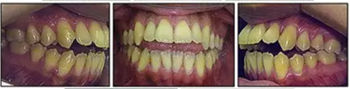

口內(nèi)相示:口腔衛(wèi)生可,下頜前牙區(qū)輕度擁擠伴齦上牙石,無齲齒、牙齦炎;開合,覆蓋5mm,休息時(shí)舌后退位,吞咽時(shí)舌前伸。

口內(nèi)相及模型:雙側(cè)磨牙、尖牙I類關(guān)系,良好的牙尖交錯(cuò)關(guān)系,覆合、覆蓋正常。